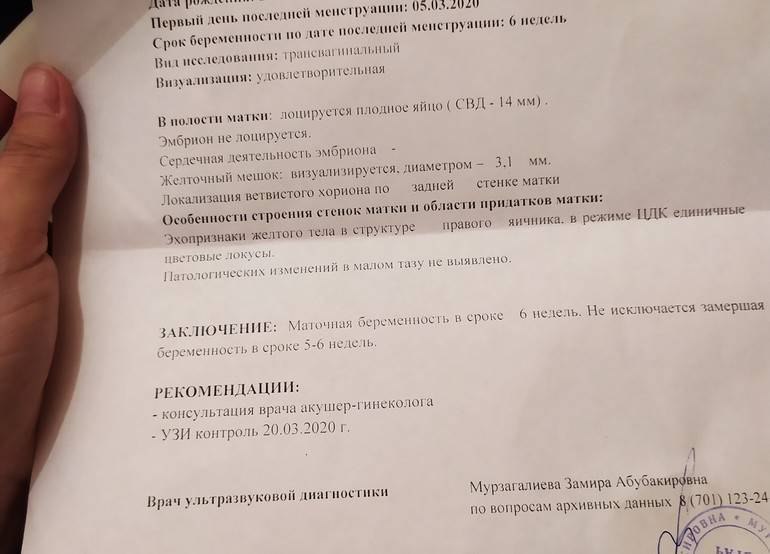

Формирование Плода в Первом Триместре: Важные Этапы